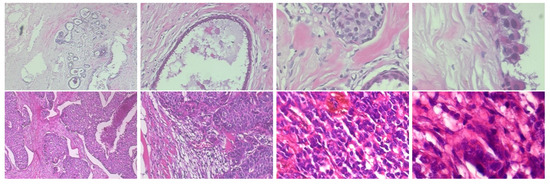

2.1. BreakHis Breast Cancer Histopathological Image Dataset

| Magnification | Malignant | Benign | Total |

| 40× | 1370 (68.67%) | 652 (32.68%) | 1995 |

| 100× | 1437 (69.05%) | 644 (30.95%) | 2081 |

| 200× | 1390 (69.05%) | 623 (30.94%) | 2013 |

| 400× | 1232 (67.69%) | 588 (32.31%) | 1820 |

| 5429 (68.64%) | 2480 (31.14%) | 7909 |